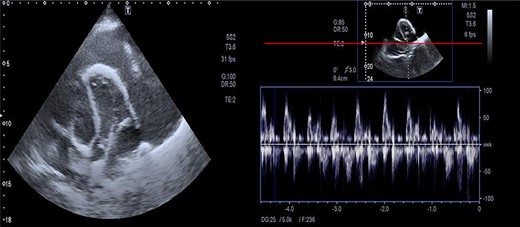

The assessment of the posterior anterior chest X-ray revealed an increased cardiothoracic ratio, a missing heart silhouette and pulmonary edema (Fig. 2). Furthermore, echocardiography evaluation revealed thickened pericardium, massive pericardial effusion, septal bounce and respiratory variation in mitral and tricuspid inflow (Fig. 3A and B).

Massive precardial effusion with a swimming heart (A); respiratory variability at the mitral inflow level (B).

All patients with heart failure should have an echocardiogram, which gives a valuable opportunity to check for constrictive pericarditis. The echocardiography’s diagnostic criteria for constrictive pericarditis are the ventricular septal shift, medial mitral e’ ≥ 9 cm/s, and hepatic vein expiratory diastolic reversal ratio of ≥0.79 [8]. Echocardiography of our case showed enlarged precordium, massive pericardial effusion, septal bounce and respiratory variability in mitral and tricuspid inflow.